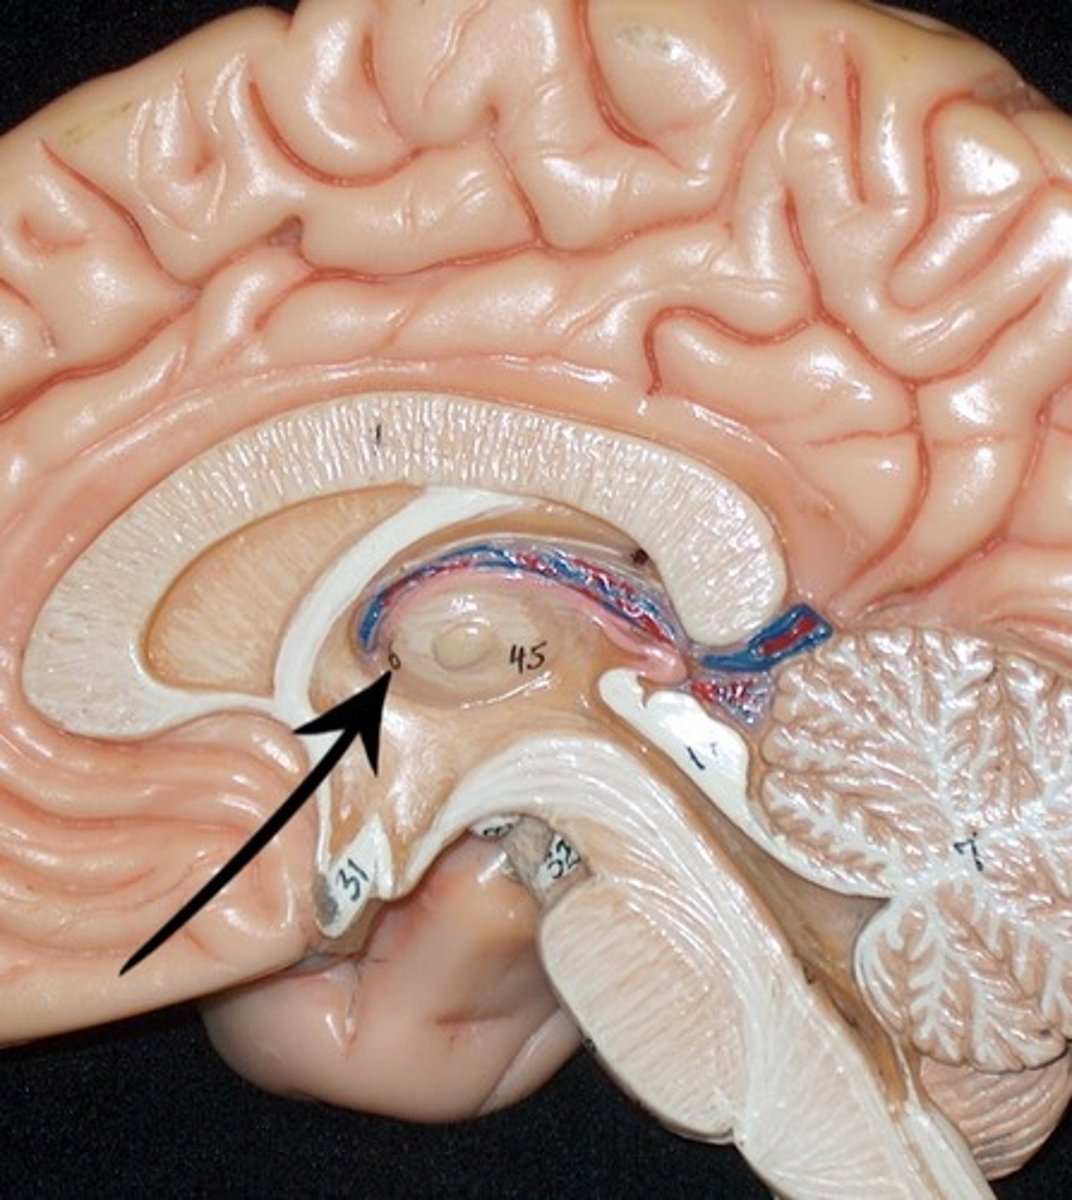

Identify the structures

Left Lateral Ventricle

Right Lateral Ventricle

Anterior horn of ventricle

Posterior horn of Ventricle

Inferior horn of ventricle

Third Ventricle

Cerebral Aqueduct

Fourth Ventricle

Dural Sinuses

Cerebral Cortex (gray matter) (Slice 2)

Cerebral Medulla (white matter) (Slice 2)

Right & Left Parietal Lobes (Slice 2)

Third Ventricle (Slice 2)

Right & Left Lateral Ventricles (Slice 2)

Choroid Plexus (blue) (Slice 2)